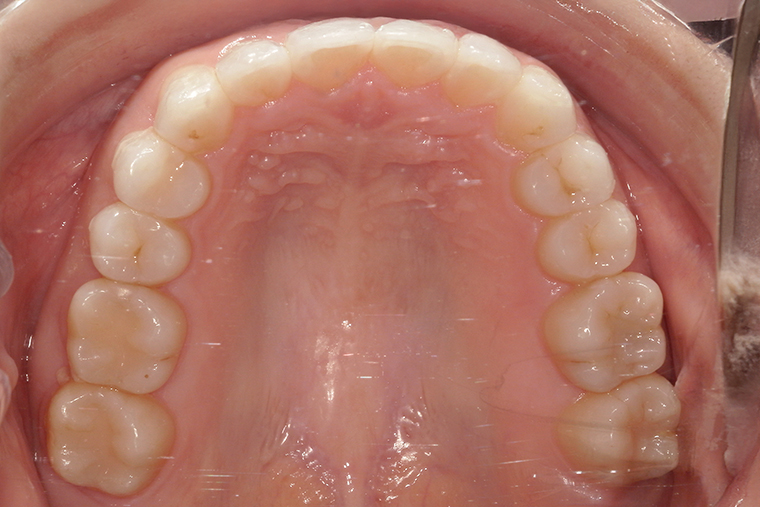

Case Study29歳女性ガタガタな歯のマウスピース矯正-矯正期間1年(2023年11月開始)